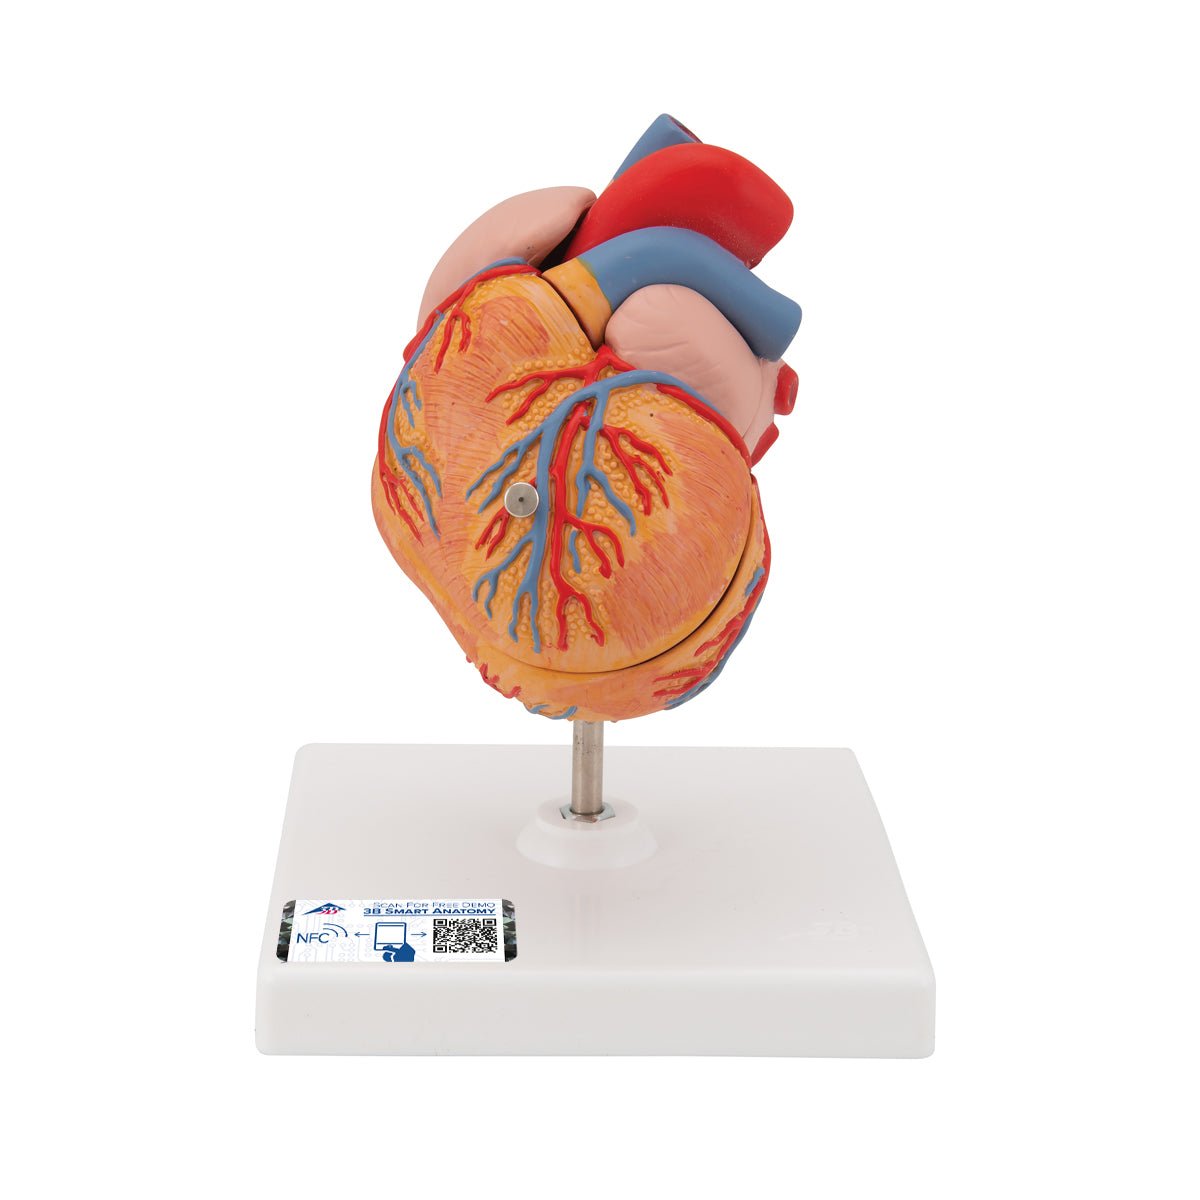

Selling anatomical models is the mainstay of eAnatomi, although we also spend a lot of resources developing our own anatomical materials such as posters. Anatomical models are used for various purposes and can show both defined tissues, organs and organ systems. Are you looking for a simple model of bone tissue or perhaps an advanced torso model based on MRI technology, you can find it all at eanatomi.com.